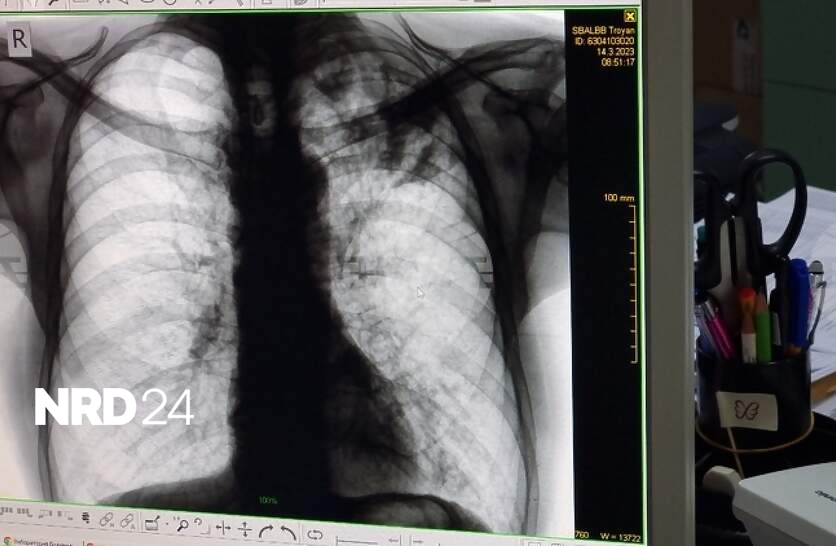

Безплатни прегледи и изследвания за туберкулоза ще се извършват в пневмо-фтизиатричното отделение на областната Многопрофилна болница за активно лечение (МБАЛ) „Свети Пантелеймон“ в Ямбол от 15 до 19 септември, съобщиха от лечебното заведение. Скринингът за заболяването ще се извършва от 12:00 до 15:00 часа в петте дни. Седмицата на отворените врати е част от кампания на Министерството на здравеопазването в рамките на Националната програма за превенция и контрол на туберкулозата в България за периода 2021 – 2025 година. По данни на Регионалната здравна инспекция през 2024 г. в област Ямбол са регистрирани 19 случая на туберкулозна инфекция, а през предходната 2023 г. заболелите са били 23-ма. Туберкулозата засяга предимно хора с нисък социален и здравен статус, затова в кампанията активно се включват и ромски медиатори, каза директорът на Регионалната здравна инспекция д-р Радостина Калчева. Кампанията се организира четири пъти в годината от здравното министерство. Целта е намаляване на заболеваемостта в страната и повишаване на обществената информираност за туберкулозата. През 2024 г. заболеваемостта у нас е 13,7 на 100 000 население, като са регистрирани 913 случая. За сравнение, през 2014 г. техният брой е 1872, като се запазва тенденцията броят на мъжете да е по-голям от този на жените.